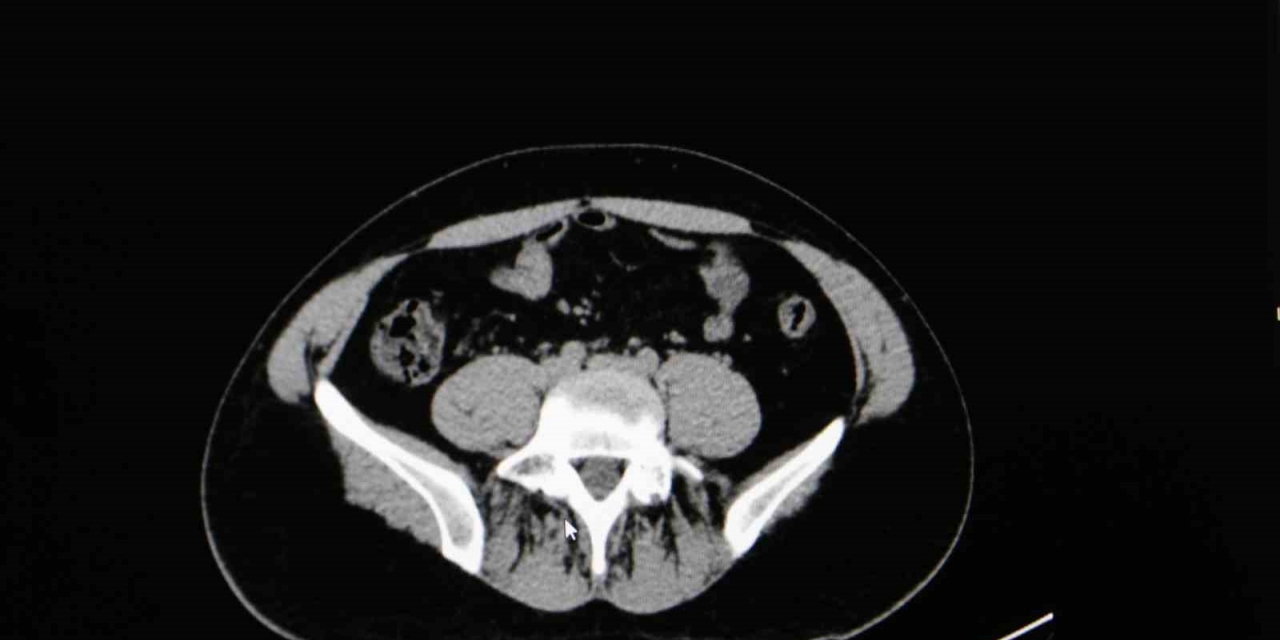

Diyarbakır Dicle Memorial Hastanesi'nde görev yapan Üroloji Uzmanı Op. Dr. Birgi Ercili "Sistit, aslında idrar torbası dediğimiz mesanenin iltihabıdır. Daha çok enfeksiyon sebepleriyle oluşur. Sistin daha çok sebebi idrar yoluna genital bölgeden ulaşan mikroorganizmalardır. Özellikle kadınlarda sistit dediğimiz durum çok fazla görülür. Çünkü kadınlarda üretra dediğimiz idrar yolu, erkeklere göre oldukça kısadır. Vajina ve anüse yakın olduğu için oradan gelen mikroorganizmaların idrar yolu aracılığıyla mesaneye ulaşması daha kolaydır. Kadınların yarısı hayatlarında muhakkak en az bir defa bu hastalığı geçirmektedir" ifadelerine yer verdi.

Sistitin sık görülen belirtilerinden idrar yanması ve az idrar yapma olduğunu ifade eden Ercili, "Sistit geliştiğinde özellikle idrarda yanma, sızı, sık sık ve az idrar yapma, damla damla idrar yapma, kasık ve alt karın bölgesinde ağrı, idrarda kan ve bulanık idrar görülebilir. Bazen de kadınlarda ilişki sonrası ağrı görülebilir. Genital hijyene çok dikkat edilmemesiyle, tuvalet temizliğini arkadan öne doğru yapılmasıyla mikropların idrar yoluna daha hızlı şekilde ulaşabildiğini görmekteyiz. Bunların dışında nemli çamaşırlarla beklemek, sık çamaşır değiştirmemek, az sıvı almak sistite sebep olabilmektedir. İlişki sonrasında da yine idrar yolunda tahriş meydana geldiği için sistit durumlarını görebilmekteyiz" diye konuştu.